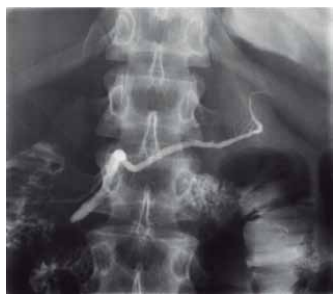

O exame radiológico contrastado com iodo, colangiopancreatografia retrógrada endoscópica, permite a visualização dos ductos biliares e pancreáticos. O ducto que encaminha uma secreção rica em bicarbonato de sódio, tripsina, quimotripsina, lipase, amilase e proteases, ao sistema digestório, é demonstrado pela radiografia a seguir:

(Arquivo pessoal; imagem usada com autorização)

A imagem refere-se ao ducto